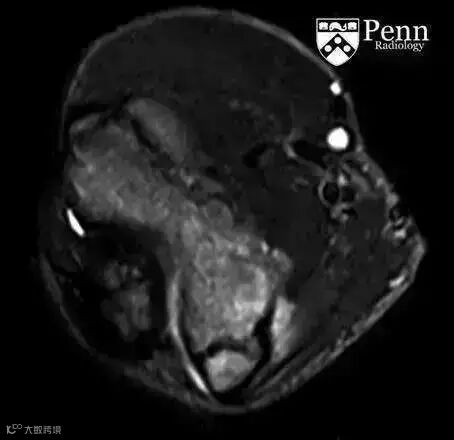

MRI:肱骨内上髁可见长T1长T2信号,骨骺板增宽。

3.病史和体格检查对诊断很关键,损伤的时间和机理,疼痛的部位、症状为诊断的关键因素。平片上肱骨内上髁炎表现为一系列征象:肱骨内上髁透亮线、分离或硬化,骨骺板增宽。MRI肱骨内上髁可见长T1长T2信号影,骨骺板增宽,有时同时可见屈肌总腱的T2信号增高。